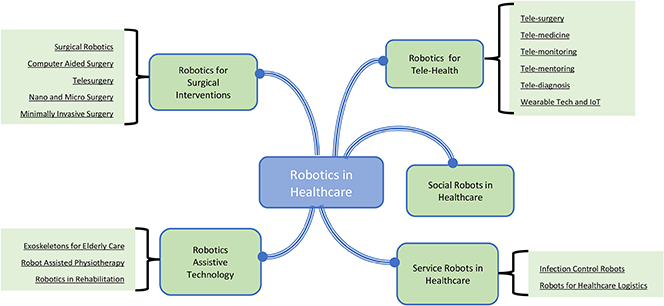

Against all of these demands and counter demands there is a widespread belief that medical and healthcare robotics is essential to transform all aspects of medicine—from surgical intervention to targeted therapy, rehabilitation, and hospital automation (figure 5.10).

Figure 5.10. Uses of robotics in healthcare.

Standard image High-resolution image5.3.2.2. Robotics and sustainable healthcare (Yang et al 2018)

As the demands on health systems grow, it is perhaps inevitable that we should turn to technology and particularly robotics, both to provide the extra capacity/productivity that will be needed by aging and rapidly increasing populations, and also to continue to enhance and improve the quality of life provided by the healthcare systems. Although robots and robotic systems represent a significant investment cost, experience in others sectors, such as manufacturing, has demonstrated that the use of robotic technology can also offer significant savings and increases in efficiency/productivity, while also contributing to the establishment of high-quality, sustainable, and affordable healthcare systems. Important application domains that could benefit include medical training, rehabilitation, prosthetics, surgery, diagnosis, and physical and social assistance to disabled and elderly people (Stahl et al 2016, Wang et al 2021).